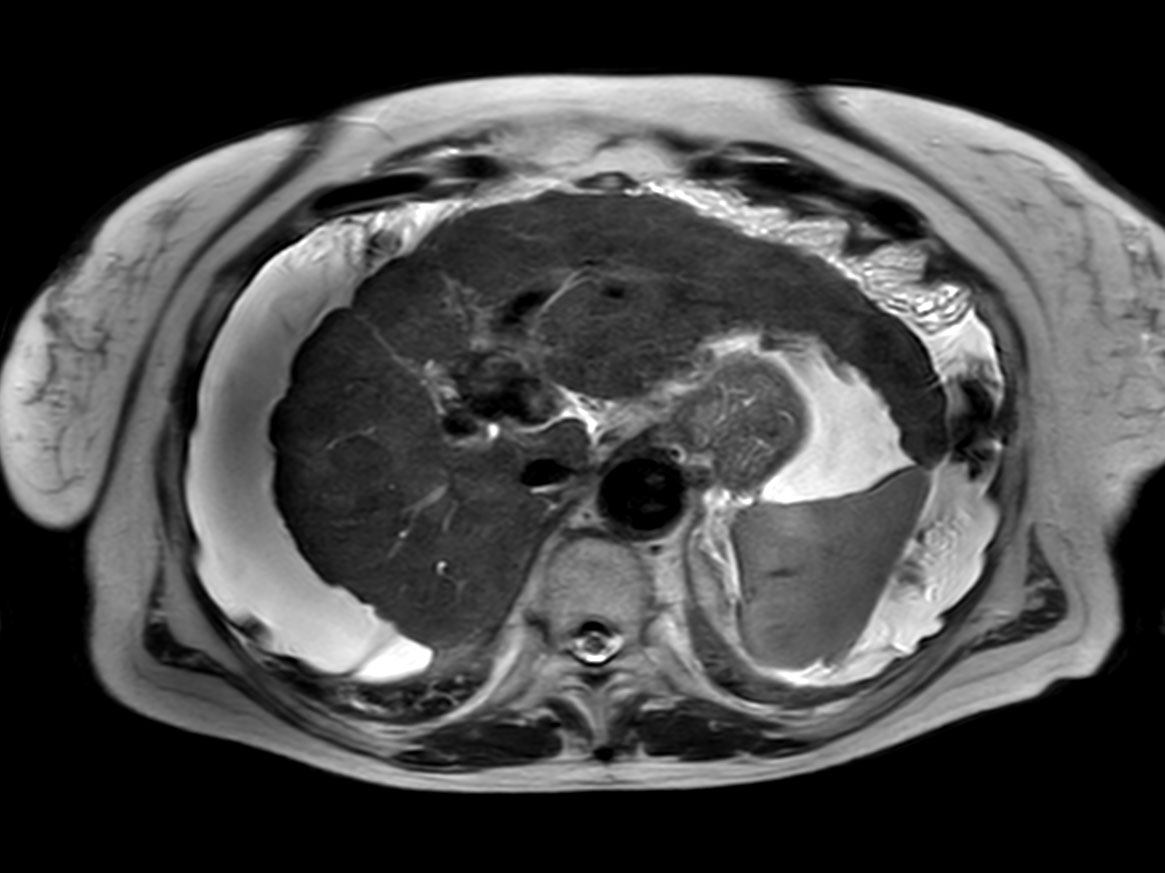

Axial T2w TSE